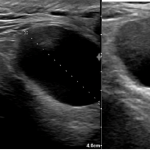

FIGURE 1 and VIDEO 2: Ultrasonography demonstrates the presence of free fluid within the peritoneal recesses, predominantly in the perihepatic and subhepatic regions (yellow asterisks). The fluid appears mildly echogenic, suggestive of inflammatory exudate rather than simple transudate. The duodenal bulb (D1 segment) is thickened and edematous. The area outlined in red demonstrates multiple hyperechoic foci with reverberation artifacts consistent with extraluminal free gas, adjacent to a focal mucosal wall defect. These findings are highly suggestive of a perforated duodenal ulcer.

FIGURE 1 and VIDEO 2: Ultrasonography demonstrates the presence of free fluid within the peritoneal recesses, predominantly in the perihepatic and subhepatic regions (yellow asterisks). The fluid appears mildly echogenic, suggestive of inflammatory exudate rather than simple transudate.

The duodenal bulb (D1 segment) is thickened and edematous. The area outlined in red demonstrates multiple hyperechoic foci with reverberation artifacts consistent with extraluminal free gas, adjacent to a focal mucosal wall defect. These findings are highly suggestive of a perforated duodenal ulcer.